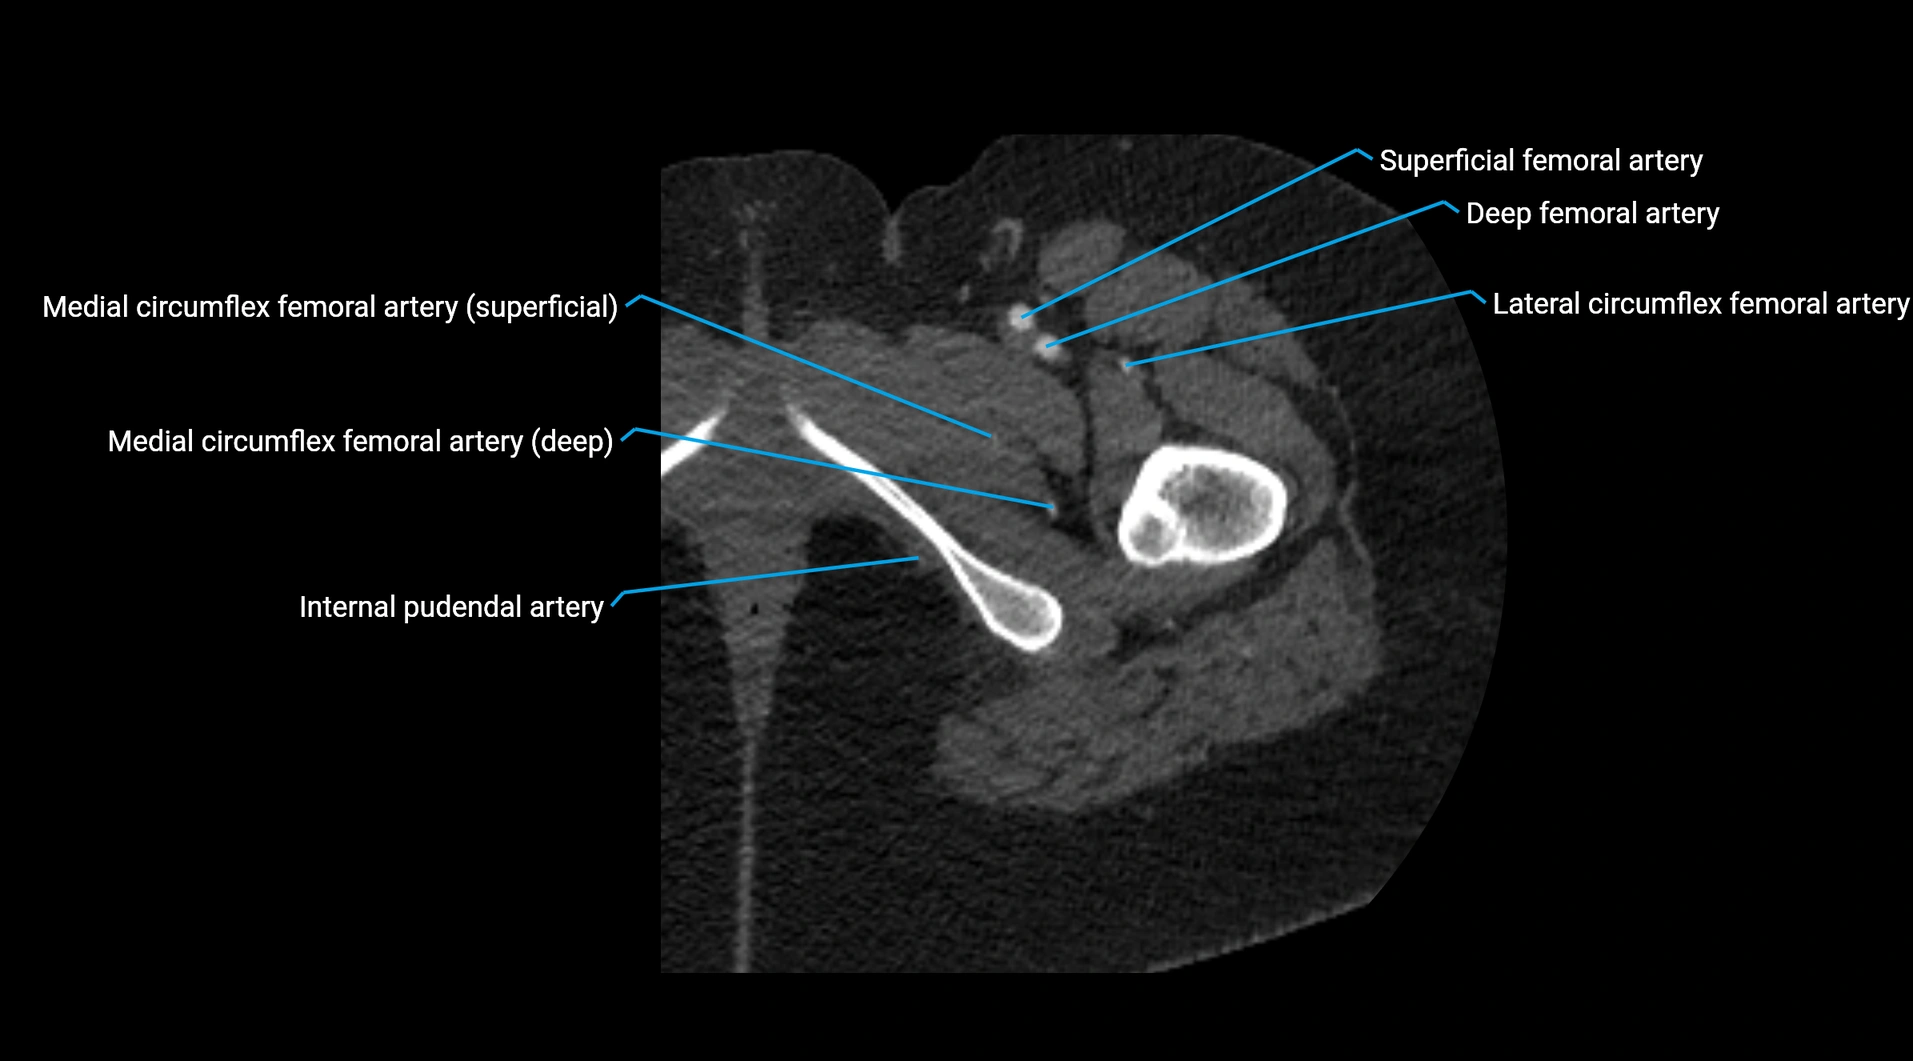

Contrast-enhanced CT (CTA):

• Gold standard for abdominal aortic imaging

• Provides excellent detail of lumen, wall, aneurysm, thrombus, and branch vessels

• Multiplanar and 3D reconstructions help in aneurysm measurement, stent graft planning, and dissection evaluation

• Detects acute rupture, traumatic injury, or occlusion with high sensitivity